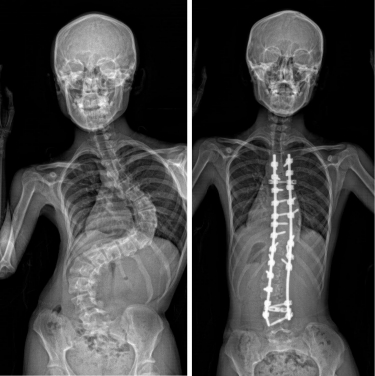

AIS is a common skeletal disorder, characterised by a lateral curvature of the spine exceeding 10 degrees, which affects 3.5% of adolescents aged between 10 and 18 in Hong Kong1. It worsens during puberty and can result in various complications including impaired cardiopulmonary functions, shortness of breath, back pain, uneven shoulders and hips, and overall poor cosmesis. These physical challenges can impact the social and psychological well-being of the affected individuals. Currently, treatment options are limited to bracing and invasive surgery after the condition develops. Preventive interventions remain unavailable, and its etiology is uncertain.

Among the patients involved in the study, Miss Lam and Miss Law were particularly instrumental in the success of the research. Both of them experienced severe scoliosis during their teenage years, and underwent surgical correction of their scoliosis deformities at the Duchess of Kent Children’s Hospital. Subsequently, 61% of Miss Lam’s family and 50% of Miss Law’s family also developed scoliosis, several of whom required surgical intervention. This SLC6A9 mutation carries an autosomal dominant pattern, which was found in the many involved members of their families.